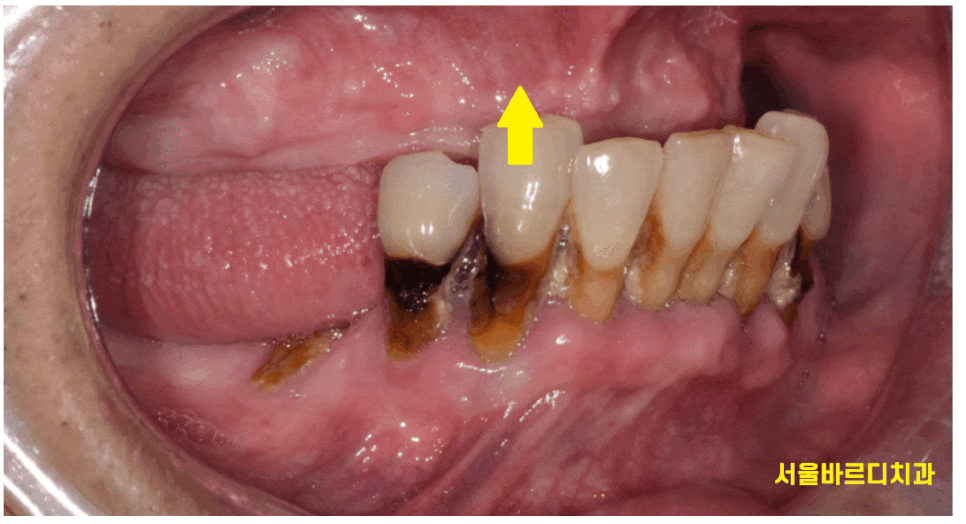

윗니는 치아가 1개도 없는 상태로

"완전 틀니"를 사용하고 계셨습니다.

하나부터 열끝까지 내 치아 말고 가짜이로 살고 계셨다는거죠~

231031

틀니를 안껴도

아래 치아가 위에 잇몸에 닿고 있었거든요~